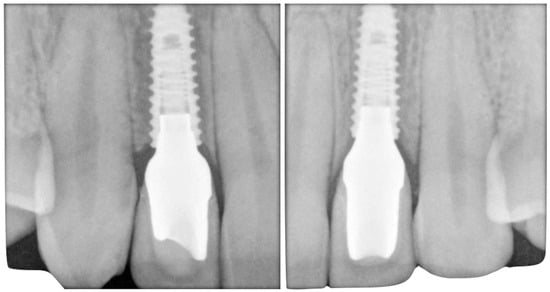

The case describes rehabilitating two congenitally missing lateral incisors in a young patient (38 years old) undergoing orthodontic treatment to create the necessary space for implant placement (Figure 1 and Figure 2). Two fibre-reinforced composite Maryland bridges (Tender Fiber Quattro—Micerium) were utilised for provisional rehabilitation (Figure 3, Figure 4 and Figure 5). Two Osstem TSIII 3.5 × 10.0 implants (1.5 mm subcrestal), two straight Osstem Zirconia abutments, and two-layered lithium disilicate crowns were employed for the definitive restoration (Figure 5, Figure 6, Figure 7, Figure 8, Figure 9, Figure 10, Figure 11, Figure 12, Figure 13, Figure 14, Figure 15, Figure 16, Figure 17, Figure 18, Figure 19 and Figure 20) [,]. The dental implant position was planned after a three-dimensional radiographic analysis in a prosthetically guided way. Patient rehabilitation was performed with an immediate post-surgery provisional (Maryland-type, cemented with a resinous cement) application. Subsequently, a delayed loading of the new provisional dental implant was retained (cemented with zinc oxide eugenol cement) and finally, definitive crowns (cemented with a definitive resinous cement) on Osstem® abutments were installed (3 months).

Figure 18. Final bilateral radiographic check.

Initial models and diagnostic wax-ups were created using silicone (Elite HD+, Zhermack) with a closed tray technique, and provisional restorations were fabricated using different colours of acrylic resin (Jet Kit®, Lang, IL, USA). Temporary restorations were then placed in position (Figure 5). A transparent resin transfer key was employed to streamline the implant’s placement. The information regarding the implant’s position was conveyed to the laboratory through a series of specialized steps. These included the installation of titanium temporary abutments sourced from Osstem® in South Korea, securing the workpiece within the transfer key using pattern resin, precision drilling on the master hard stone model (Figure 6, Figure 7 and Figure 8), and an accurate placement of analogues in this model by employing a recasting technique with hard stone material (Figure 9). After revealing the implanted components, provisional restorations were promptly delivered as part of the uncovering procedure to encourage optimal soft tissue healing (Figure 10). Adjustments were made to the emergence profile to condition the surrounding soft tissues properly, and specialized conditioning procedures were carried out (Figure 11 and 12). Before and after conditioning, the changes in the profiles were documented (Figure 13). The new profiles obtained were transferred to the master model by mounting the modified provisional restorations with analogues, and a new artificial gum was created through recasting (Figure 14). Once the soft tissues had healed correctly, guided by the modified and polished provisional as in Figure 11, it was possible to transfer the mucosal profile onto the master model. By removing the provisionals from the oral cavity, they were then positioned on the master model, corresponding to the dental implant analogues in the master model. The master model that had previously been modified and freed from any over contours or undercuts was relined at this point with a laboratory silicone to simulate the profile of the mucosa. The abutments were customised using ceramic and fluorescence techniques to achieve optimal emergence profiles (Figure 15). Gingival profiles were assessed, and the abutments were inserted accordingly (Figure 16 and Figure 17). The final stage involved the placement of crowns, which were fabricated using ceramic material (E.max ceram®, Ivoclar, Naturno, Italy). A last radiographic check was performed to ensure a proper alignment and fit of the restorations. The case was considered completed, and aesthetic integration was achieved. Overall, this case report encompassed various steps, including an initial assessment, diagnostic procedures, provisional restorations, implant placement, emergence profile modifications, abutment customisation, crown placement, and the final evaluation of the completed case.